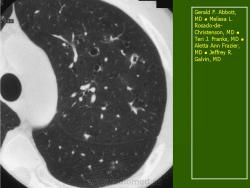

В 5 наблюдениях (21%) из больных с распространенной формой заболевания отмечались изменения в легких в виде обогащения, избыточности легочного рисунка, его деформации по сетчато-петлистому типу, очаговых теней. Корневая и медиастинальная аденопатия отсутствовали. В 1 случае в легких выявлена киста, которая периодически осложнялась нагноением (Рис. 4).

Поражение легочной ткани (рис. 22) свойственно любому возрасту. Часто больные имеют общие симптомы — лихорадку, слабость, реже — кашель, одышку, боли в грудной клетке. На рентгенограммах отмечается деформация и усиление легочного рисунка и микроузловые инфильтративные тени. Поражение костного мозга (с наличием клеток Лангерганса) сопровождается цитопенией периферической крови.

Рис. 22. Поражение легких при Лангер-гансово-клеточном гистиоцитозе.